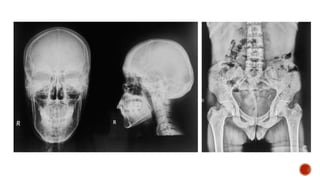

 AP and lateral radiographs of the skull show multiple tiny lucent areas with areas of

sclerosis in between, giving rise to salt and pepper skull appearance.

 Radiographs of both the legs, knees and left humerus show diffuse osteoporosis with

few well defined lytic areas.

 Radiograph of the hand shows osteoporosis with coarse trabeculations of the

phalanges with mild erosions along tteh radial aspect.

HYPERPARATHYROIDISM

FINDINGS

 Osteopenia

 Subperiosteal resorption: classically along radial aspects of phalanges

 Floating tooth

 Subchondral resorption (lateral end of clavicles, pubic symphysis, sacroiliac joints)

 Subligamentous resorption(ischial tuberosity, trochanters)

 Brown tumors(more common in primary)

 Salt and pepper skull

 Rugger jersey spine

 Secondary and tertiary hyperparathyroidism may be associated with osteosclerosis of

renal osteodystrophy and osteomalacia of vitamin D deficiency

 Superior and inferior rib notching may be seen